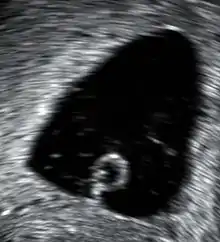

- كيس حمل فارغ [الإنجليزية] في هذه الحالة ينمو كيس الحمل ويكبر بدون جنين